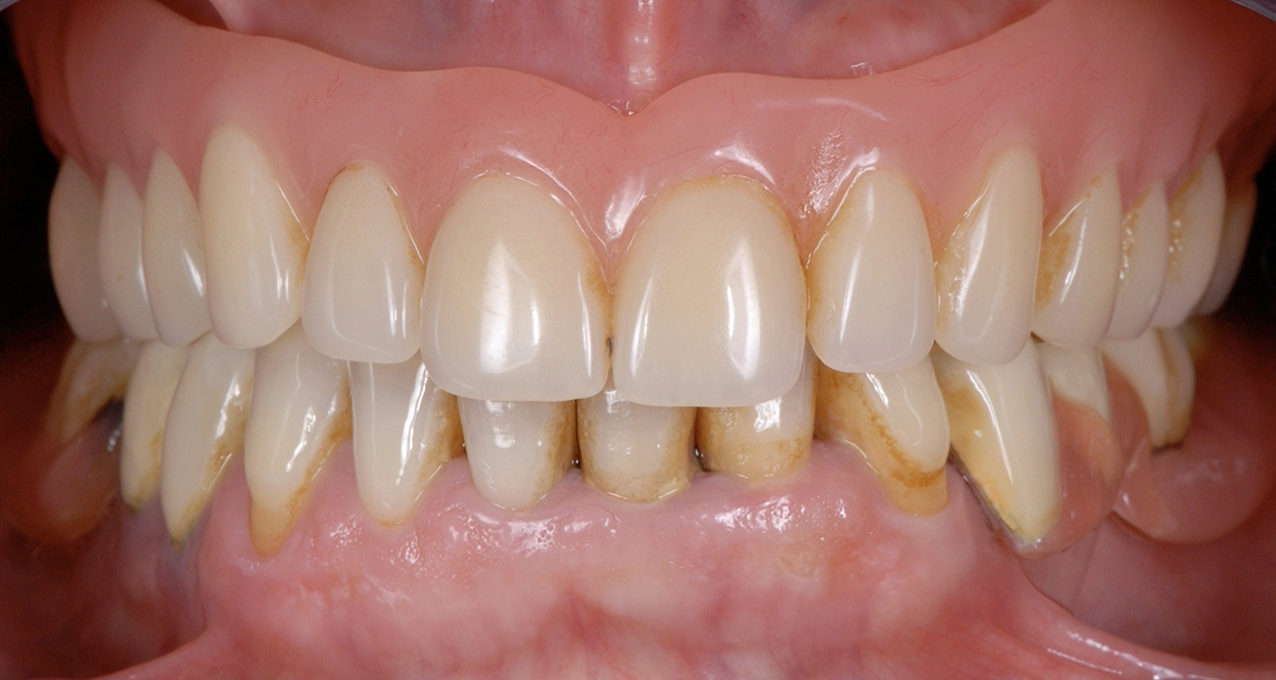

We recently completed a same-day digital full-arch implant treatment using in-office 3D printed stackable surgical guides and a 3D printed hybrid prosthesis. prosthesis. Advance your implant dentistry skills with the industry-leading Full Arch Implant Course for Dentists offered by gIDE Dental Institute. This comprehensive program is specifically designed for clinicians who want to master full-arch rehabilitation using predictable, evidence-based protocols. Whether you are new to full-arch procedures or looking to enhance your expertise, this course provides the clinical confidence and hands-on experience needed to succeed in modern implant dentistry.